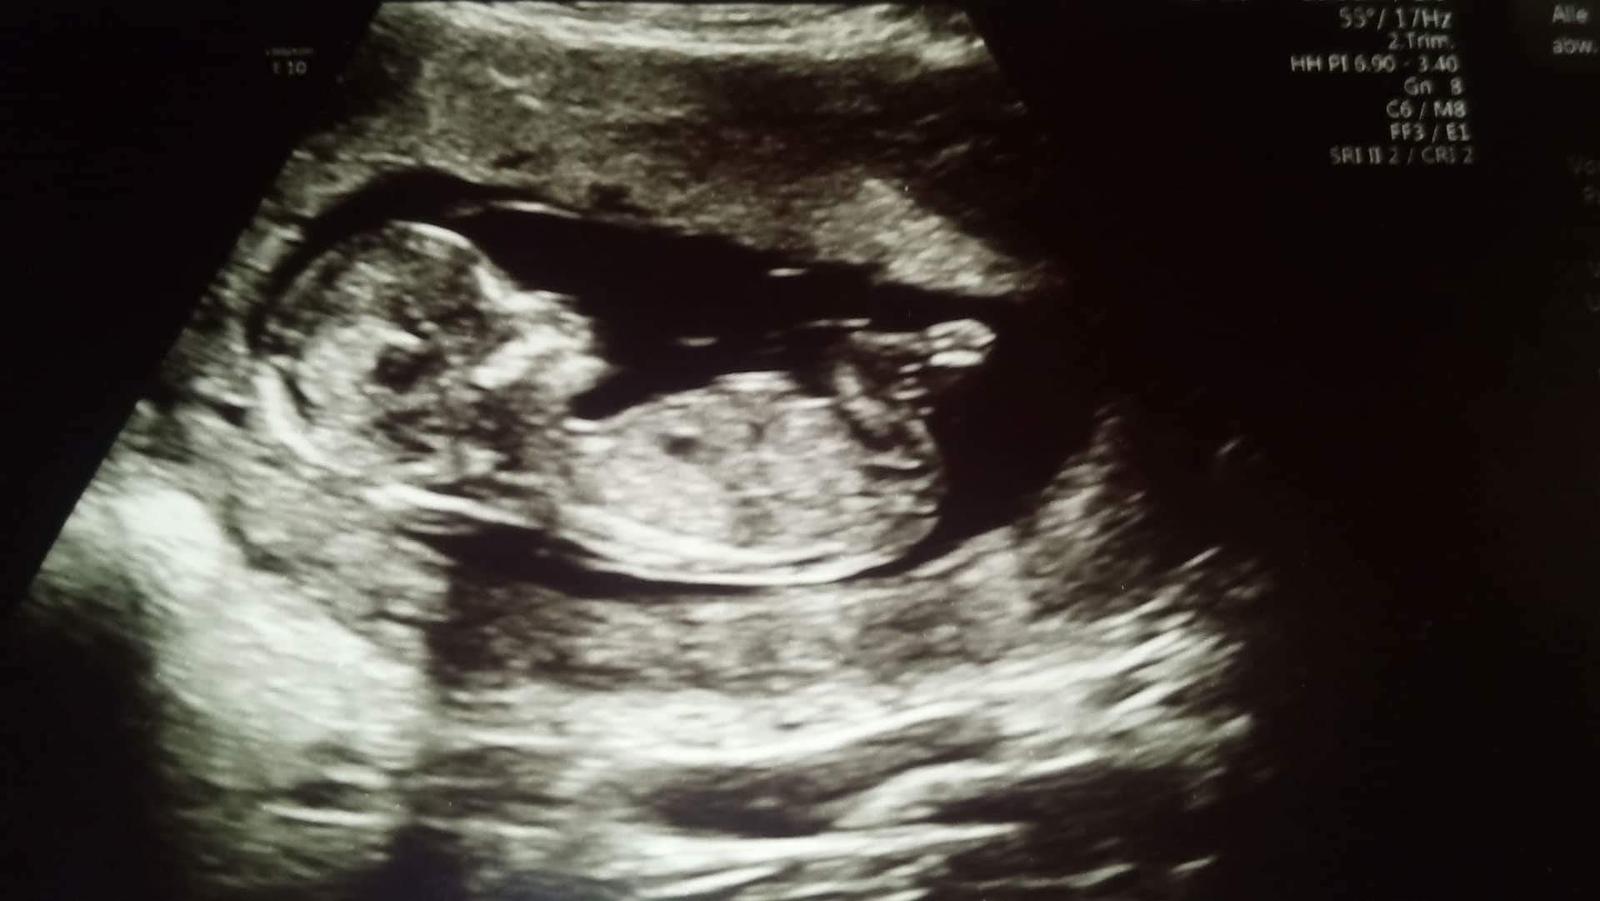

Těhotenský test. Dávám fotku. Co myslíte?

Tak nevim ... ☹ Dávám fotku, skuste posoudit...